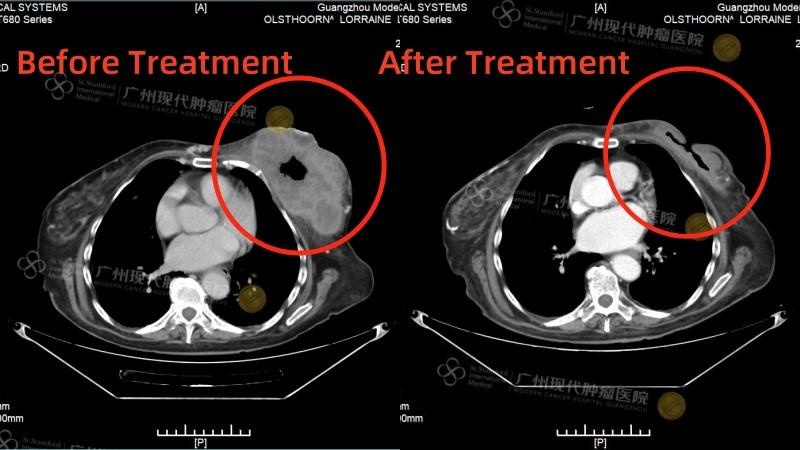

Сравнение КТ лёгких до и после лечения. Опухоль лёгких практически инактивирована

(Слева: до лечения, справа: после лечения)

Лечение дало ошеломляющие результаты: • После двух процедур КТ показало уменьшение очага в легком, а колоноскопия - значительное сокращение опухоли в кишечнике. • Исчезли мучительные симптомы: кашель и кровавый стул. • После семи сеансов опухоль в легком была практически полностью инактивирована, а в кишечнике - уменьшилась на 90%. Путь не был усыпан розами. Однажды у Радика резко упал уровень тромбоцитов, что грозило опасным кровотечением. В момент отчаяния именно настойчивость и профессионализм его лечащего врача, доктора Аденана, и всей команды спасли ситуацию. Быстро проведенная симптоматическая терапия стабилизировала состояние, и лечение было продолжено.